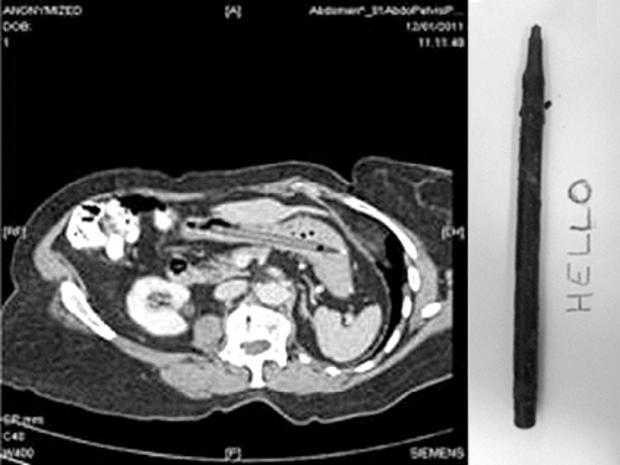

Pen lodged in stomach for 25 years

In a case published in British Medical Journal Case Reports, a woman had a pen lodged in her stomach for 25 years. When doctors removed the pen, it still could write.